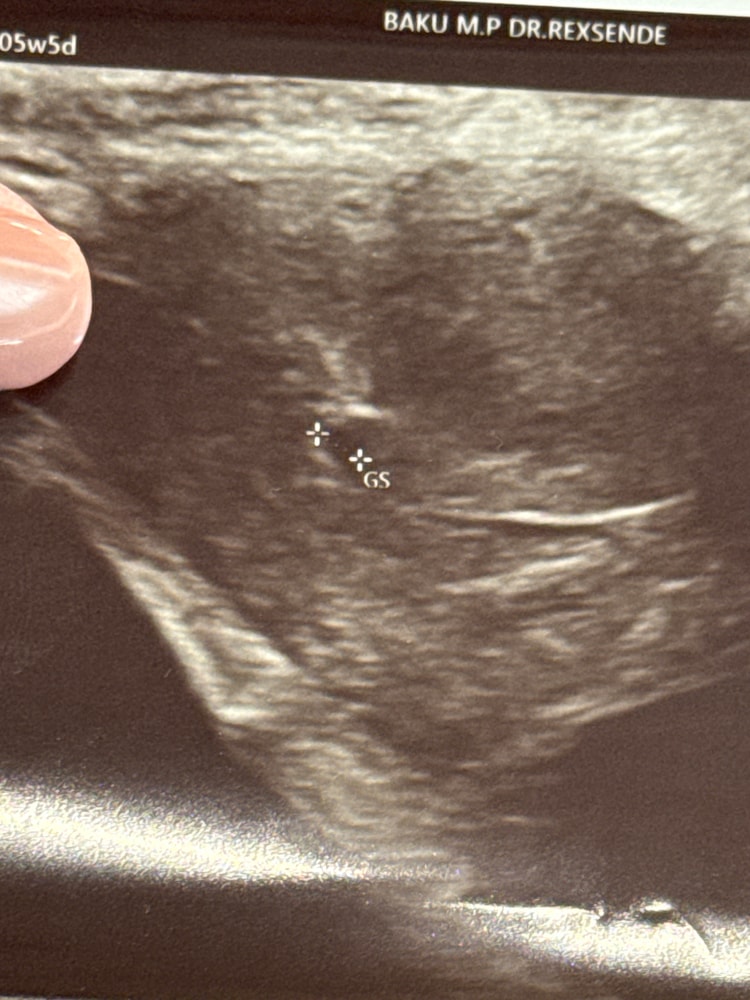

Обследования, узи, анализыДобрый день делала узи вчера на 5+5 неделе, смотрели через живот ,увидели только плодное яйцо размером 3.7 мм . Сказали приходить через 2 недели. Срок по узи 5+1. Я очень волнуюсь вдруг анэбриония или еще что то( Кто сталкивался? Овуляция была поздняя примерно 12 го сентября

Маленькое плодное яйцо еще для желточного мешка и эмбриона ... Ждите пока вырастет

В 5 недель еще ничего не видно на УЗИ)

Правильно врач сказал, придете через 2 недели, будет вам и эмбрион и сб)

Не делают узи на таком малом сроке через живот.

Кроме ПЯ они, конечно, через живот не увидят ничего.

Ровно в 5 недель на узи через живот увидили только ПЯ, в 5+1 трансвагинально уже увидели бриллиантовое колечко и в 5+6 трансвагинально увидели эмбрион и сердцебиение. Делали так часто т.к. лежала в стационаре с кровотечением